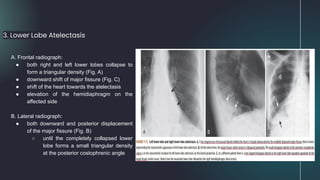

A. Frontal radiograph:

● both right and left lower lobes collapse to

form a triangular density (Fig. A)

● downward shift of major fissure (Fig. C)

● shift of the heart towards the atelectasis

● elevation of the hemidiaphragm on the

affected side

B. Lateral radiograph:

● both downward and posterior displacement

of the major fissure (Fig. B)

○ until the completely collapsed lower

lobe forms a small triangular density

at the posterior costophrenic angle

3. Lower Lobe Atelectasis

● In the critically ill patient, atelectasis occurs most frequently in the left lower lobe

○ Always check the left hemidiaphragm to be sure it is seen in its entire extent through the heart

shadow

■ left lower lobe atelectasis will manifest by disappearance (silhouetting) of all or part of the left

hemidiaphragm (Fig. C)